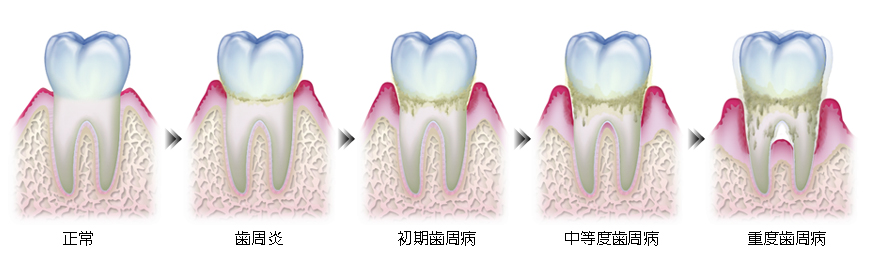

歯周病とは

| 歯垢や歯石 | 歯周病(歯槽膿漏) のもっとも大きな原因は 「食べカス」 などにより発生する歯垢や歯石です。 歯の周囲に付着する細菌性の歯垢や歯石が、歯肉と歯の根の間の、いわゆる歯周ポケットの中に侵入し、その中で細菌が繁殖をくりかえすことによって、 歯周病を進行させていきます。 |